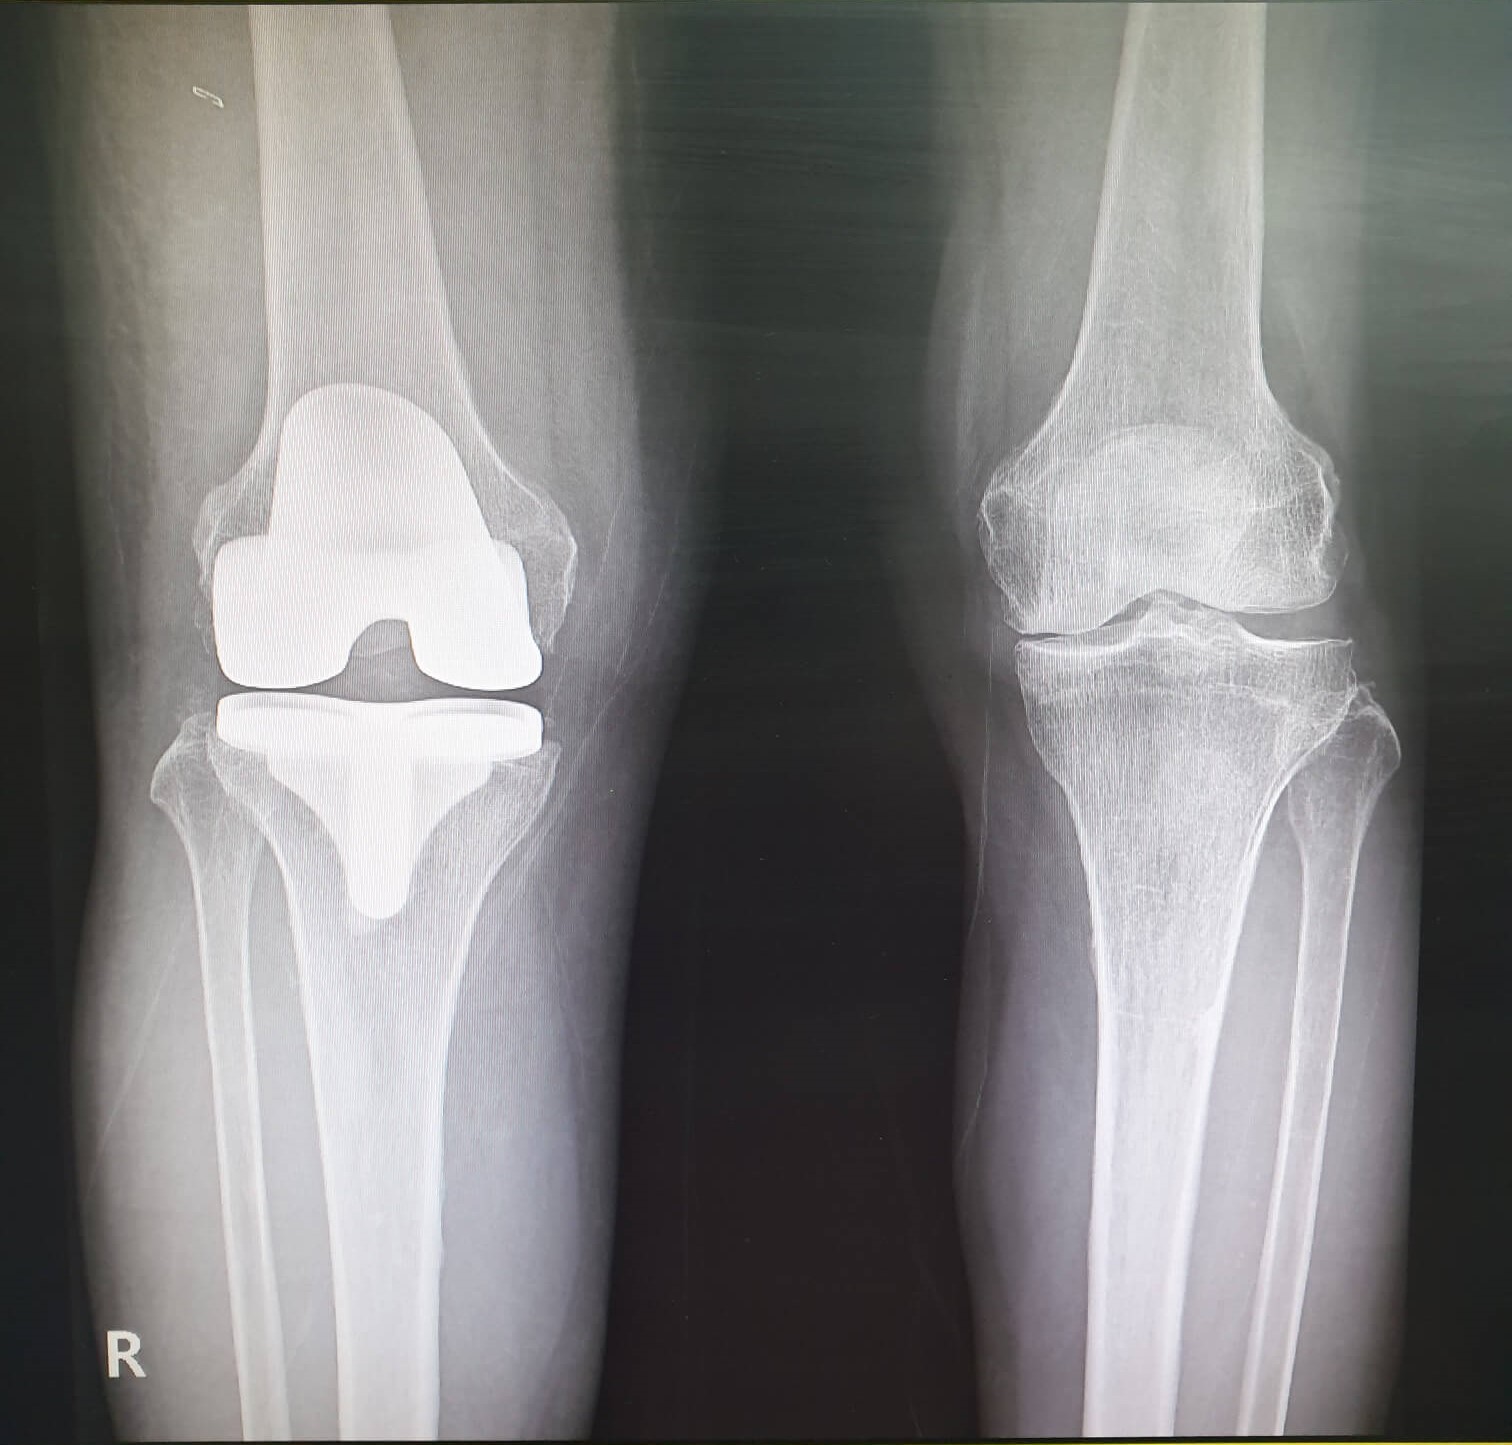

대상질환 : 건강보험급여 '인공관절치환술(슬관절)' 인정기준에 준하는 질환자

여기서 말하는 슬관절 인공관절치환술이 바로 무릎인공관절수술입니다.